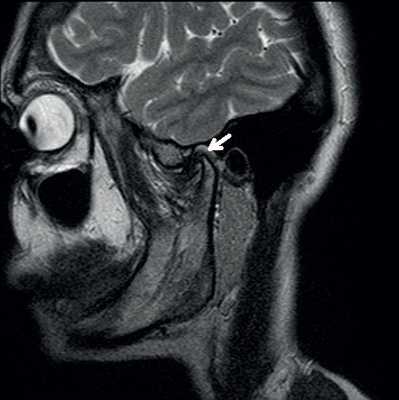

КТ, МРТ при пигментном ворсинчато-узелковом синовите височно-нижнечелюстного сустава (ВНЧС)

- Магнитно-резонансная томография. Виллонодулярный синовит видно на снимках МРТ, поскольку такое исследование одновременно показывает состояние костей и мягких тканей.

МРТ — предпочтительный метод визуализации при таком заболевании. Рентгенологи в клиниках ЦМРТ ставят диагноз по результатам сканирования.

- Опухоли (синовиальный хондромастоз, пигментный виллонодулярный синовит, неоплазма). Сопровождаются такими симптомами, как боль, отёк, тугоподвижность сустава.